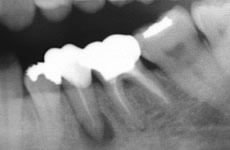

根の先の病気

主に虫歯が原因で、細菌が歯の中に通っている神経の管を通って神経自体に炎症を起こしたり、根の先に膿を作ることがあります。感染してしまった部分をきれいにとり、清掃をして、きれいになったところで細菌が増えないように薬をつめます。